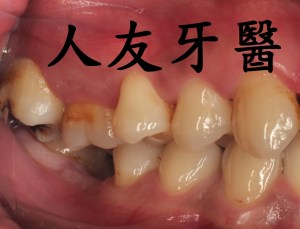

植牙後常見的問題,人工植牙雖然有著不會蛀的金屬質地,但它附屬的地基「齒槽骨」和周圍覆蓋的牙肉跟我們自己的牙齒一樣,植牙周圍若是清潔不乾淨,也會產生牙周病,造成「植體周圍炎」。

但尚未影響到硬組織,被稱為植體周圍黏膜炎;若已破壞到周遭骨頭,被稱為植體周圍炎。若周遭骨被破壞,最後可能造成植體失敗,需要移除,植牙等於做了白工。分析造成植體周圍疾病的原因,主要是細菌,如牙菌斑;咬合力量過大、牙套完成時殘留的黏著劑未清潔乾淨、製作不當的牙套也會。